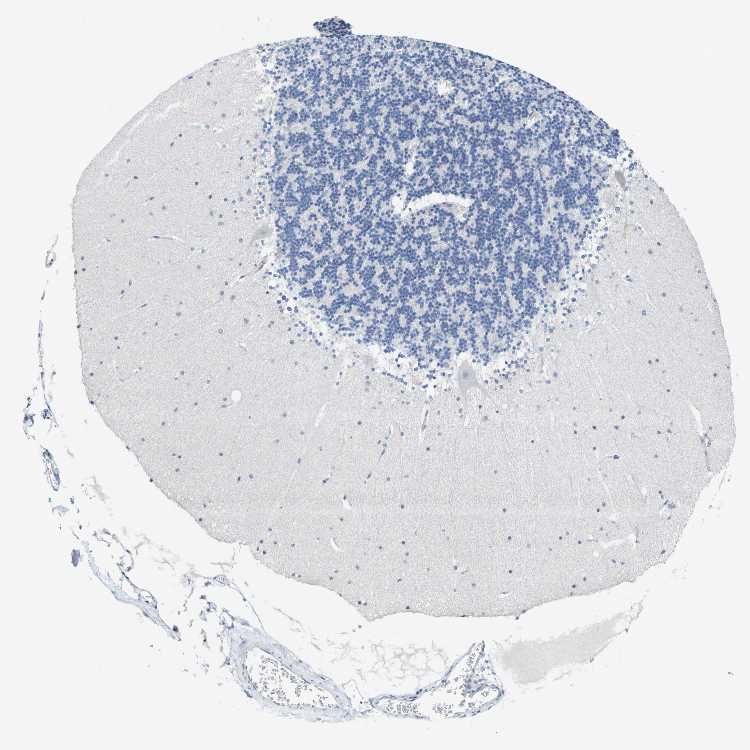

BRAIN CEREBELLUM Show tissue menu

CEREBELLUM - Expression summary

CEREBELLUM - Antibody stainingi

Antibody staining in the annotated cell types in the current human tissue is reported as not detected, low, medium, or high, based on conventional immunohistochemistry profiling in selected tissues. This score is based on the combination of the staining intensity and fraction of stained cells.

Each image is clickable and will lead to virtual microscopy that enables deeper exploration of all samples and also displays staining intensity scores, fraction scores and subcellular localization as well as patient and tissue information for each sample.

Antibody HPA038494Antibody CAB017520

Purkinje cells MediumNot detected

Cells in granular layer Not detectedNot detected

Cells in molecular layer Not detectedNot detected